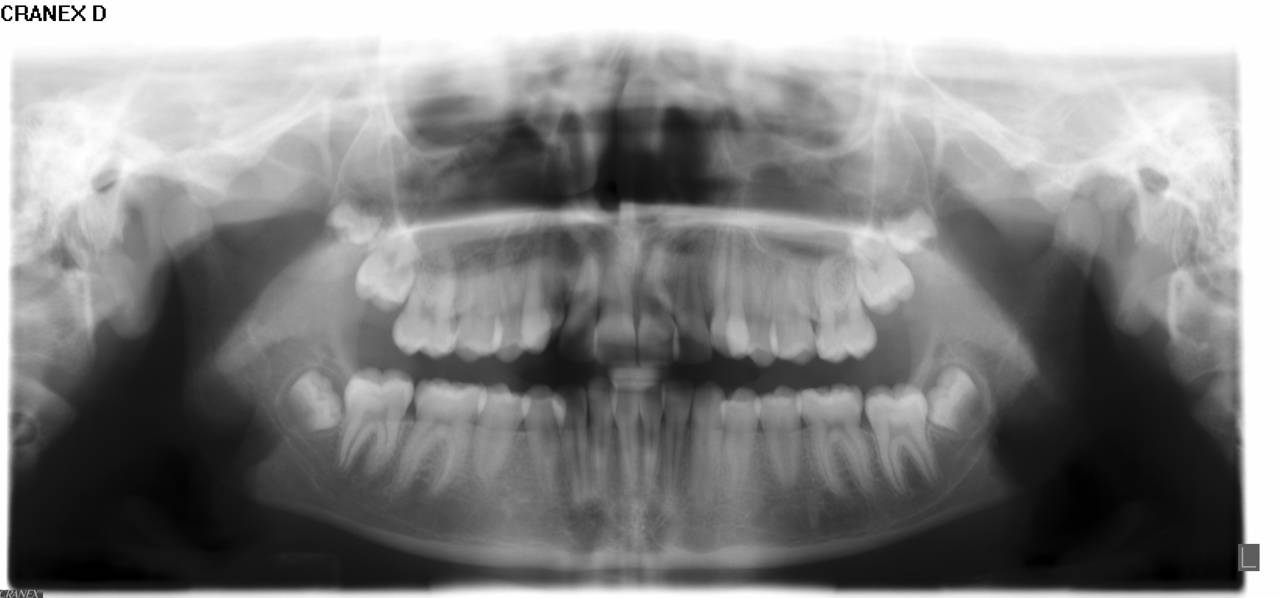

- Panorama viser, om alle tænder er anlagt, og om tandrødder og kæbeled ser normale ud.